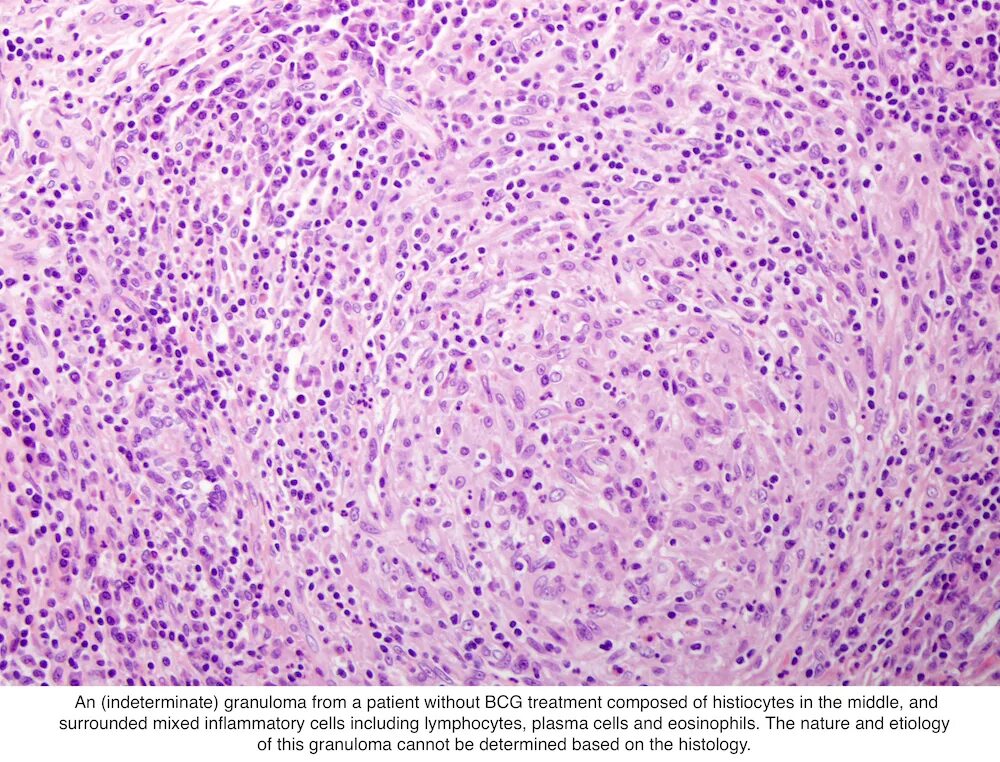

Клетка типа инородных тел